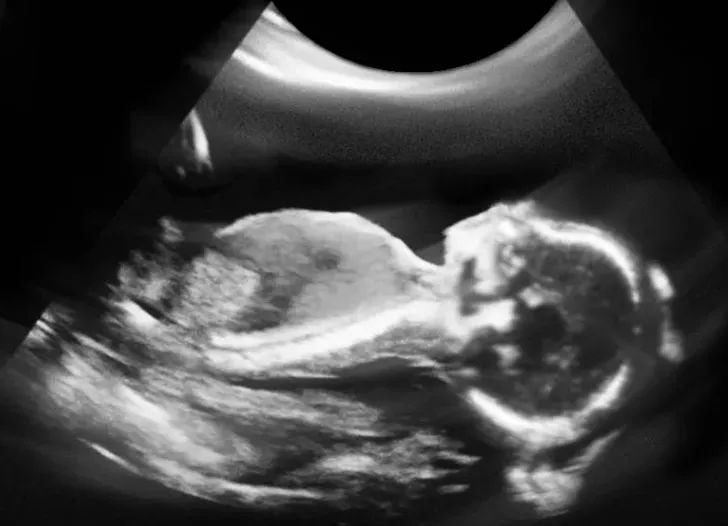

重视孕前、孕期及产后检查,做好一、二、三级预防是孕育健康宝宝的有力保障,而产前进行系统的超声检查就是这些保障措施中重要的一项。它不仅能让准妈妈提前看到宝宝,更能为医生提供相关信息,通过分析宝宝在子宫内的情况,来帮助医生评估胎儿的健康和生长发育情况,是孕期的重要辅助检查手段。

可是,在拿到超声检查报告单的时候,不少孕妈却是一脸懵圈:这么多数值,它们认识我,我不认识它。好想知道每一个数据是什么意思,难道只能一个一个地问医生吗?别着急,今天小编就带大家一起解读超声报告单上的奥秘!